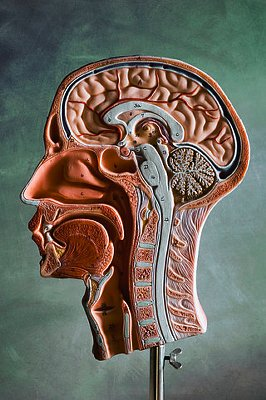

公司生產的生物液體粘貼,外科醫生注射到血液中受災地區的頭蓋骨的動脈瘤發生時。這種醬是小量生產,是相當昂貴的。實現適當的一致性、糊粘度必須非常精確。如果太薄,但不會達到適當的阻塞,如果太厚,它不能安全注射。生物技術企業需要一個易于使用的粘度,從而準確地測量最少數量的藥品樣品可能的。

該公司已經在使用他們的開發實驗室中劍橋粘度計和有第一手的經驗與傳感器的精度和可靠性。他們面臨著一個特殊的挑戰,然而,當它來測量生物粘貼的粘度,因為它要求他們與微量樣品粘度計工作的有價值的材料。該公司之所以選擇了CVI 公司的VISCOlab 5000型微量樣品粘度計,因為它只需要75 micro-liters樣品的研究和生產應用程序。